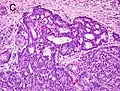

Cribriform pattern: Gleason grade 4

Gleason score 7 (3+4) with minor component of cribriform glands